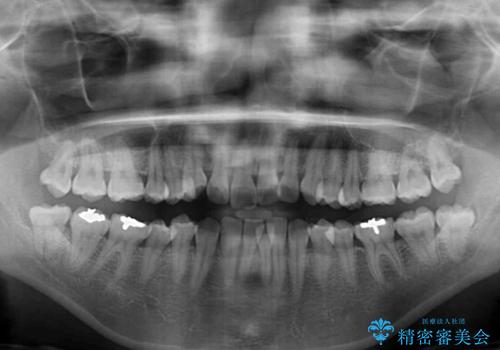

- 上下前歯のデコボコを気にして来院された患者様です。

デコボコを解消する過程で、歯列の拡大により口元が突出する可能性があったため、4本の親知らずを抜歯しておき、歯列全体が後方に移動するように設計し、インビザラインにて矯正治療を行うこととしました。